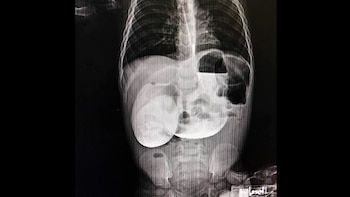

La evaluación médica determinó la existencia de una obstrucción en el intestino delgado, lo que impedía el tránsito normal de los alimentos por el sistema digestivo. La cirujana pediatra Rosa Murphy Hoyos explicó que el paciente presentaba atresia duodenal, una condición congénita que aparece durante el desarrollo fetal cuando el intestino no se forma de manera adecuada. En este caso, una membrana bloqueaba totalmente el paso de los alimentos.

Según la especialista, “lo habitual es detectar esta condición en el primer mes de vida, pero en este caso el menor sobrevivió con una obstrucción parcial que, con el tiempo, agravó su estado nutricional”. Esta situación poco común dificultó el diagnóstico temprano y permitió que la complicación se intensificara progresivamente.

De acuerdo con la Biblioteca Nacional de Medicina de Estados Unidos, la atresia duodenal corresponde a una malformación congénita caracterizada por una obstrucción en el intestino, la cual suele manifestarse con vómitos —ya sean biliosos o no— en las primeras horas de vida, especialmente tras la administración inicial de alimento por vía oral. Esta afección se asocia frecuentemente con polihidramnios durante el embarazo y figura entre las principales causas de bloqueo intestinal en el periodo fetal.

El diagnóstico puede establecerse mediante ecografía prenatal, herramienta que facilita la identificación temprana del problema. En ausencia de una detección antes del nacimiento, la evaluación comienza con una radiografía simple de abdomen, método que permite observar signos característicos de la patología. Si surge la necesidad de mayor precisión, se emplean estudios con contraste para visualizar el trayecto intestinal.

La confirmación definitiva puede lograrse a través de una serie gastrointestinal superior limitada utilizando bario, o con una ecografía en la que se administra agua o una solución como Pedialyte. En este contexto, la tomografía computarizada resulta de escasa utilidad y rara vez se emplea para valorar este tipo de obstrucción congénita.